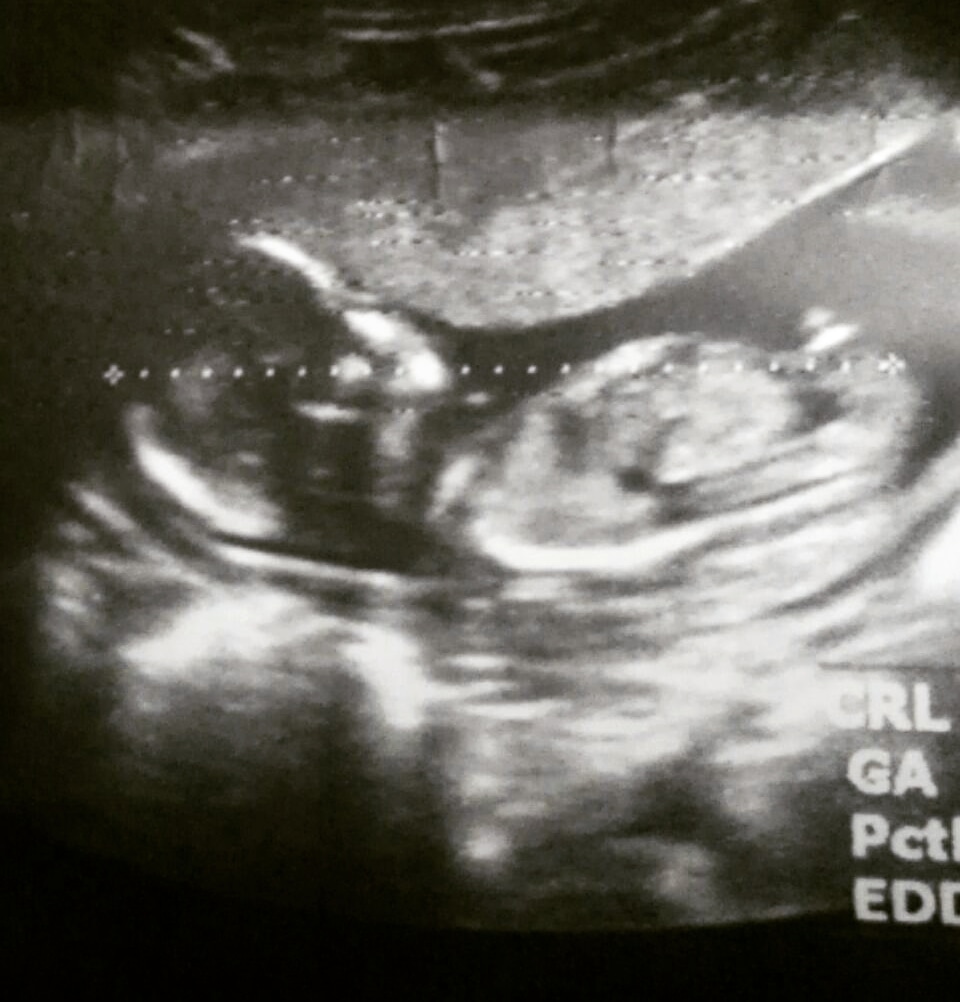

جنین برآمدگی کوچکی بین پاها دارد که برای پسرها، آلت تناسلی مردانه و کیسه بیضه و برای دخترها، لبیا می باشد. برآمدگی پسر زاویه ای بیشتر از سی درجه دارد و برآمدگی دختر به صورت خطوط موازی با بدن است.

مطالعه تفاوت جنین دختر و پسر در سونوگرافی در مجله ونوس https://mag.farzand.net/?p=25823